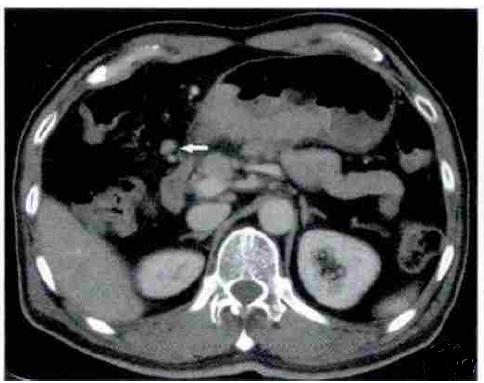

上图可看到胃窦小弯侧软组织密度结节,大小约18mm×17mm,平扫CT值约37HU,增强扫描动脉期可以明显强化,CT值约134HU,门脉期持续呈高强化,延迟期强化减低。余黏膜面未见异常强化,浆膜面光整。胃周未见明显肿大淋巴结。

动脉期明显强化,门脉期持续强化,延迟期强化减低,门脉期达到强化峰值;

动脉期病变斑片状强化,门脉期强化范围逐渐增宽;

黏膜面未见异常强化,浆膜面光整。